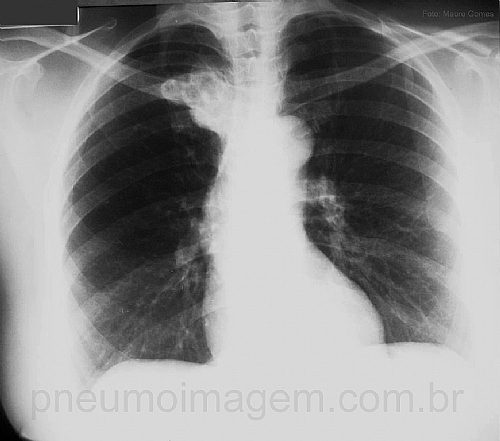

Observe essa radiografia com essa massa paratraqueal à direita. Com base somente na incidência em PA, onde se localiza essa lesão?

Please note that right paratracheal mass. Where is this injury?